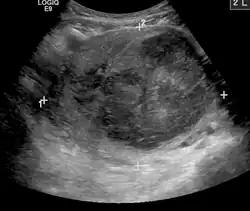

A very large (9 cm or 3.5 in) fibroid of the uterus causing pelvic congestion on US

Chronic pelvic pain

• Veins have one-way valves that help blood flow toward the heart. If the valves are weak or damaged, blood can pool in veins, making them swell. When this happens near the pelvis, it is called pelvic congestion syndrome, which can lead to chronic pain beneath the level of the belly button.

• Pelvic congestion syndrome usually affects women who have previously been pregnant, because the ovarian veins and pelvic veins had widened to accommodate the increased blood flow from the uterus during pregnancy. After the pregnancy, some of these veins remain enlarged and fail to return to their previous size, causing them to weaken and allowing blood to pool.[42]

• An interventional radiologist can offer a minimally invasive treatment option for pelvic congestion syndrome: ovarian vein embolization

• Ovarian vein embolization is a same-day treatment which takes place in an interventional radiology suite. The interventional radiologist gains access through a large vein in the groin, called the femoral vein, by using a small catheter, which is a flexible tube like a strand of spaghetti. The catheter is moved through the vein to the enlarged pelvic veins, allowing the introduction of embolic agents, which are medications that cause the vein to seal off and relieve the painful pressure.[43]

• This treatment can be less expensive than surgery and is much less invasive.